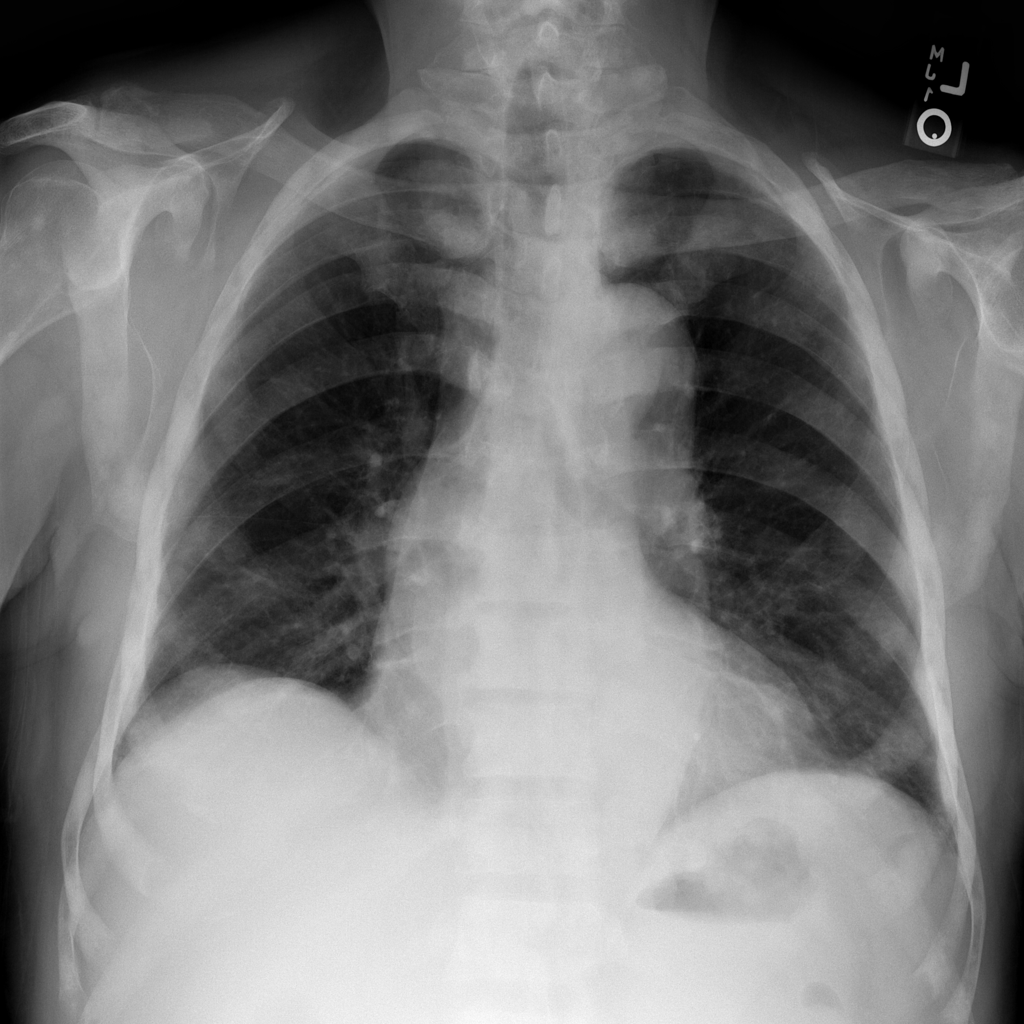

Examine an X-ray with imageio¶

Let’s begin with a simple example using just one X-ray image from the ChestX-ray8 dataset.

The file — 00000011_001.png — has been downloaded for you and saved in the

/tutorial-x-ray-image-processing folder.

1. Load the image with imageio:

3. Import matplotlib and display the image in a grayscale colormap:

import matplotlib.pyplot as plt

fig, ax = plt.subplots()

ax.imshow(xray_image, cmap="gray")

ax.set_axis_off()